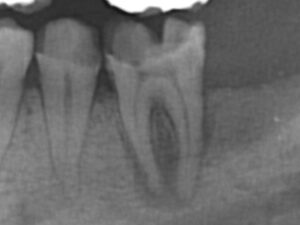

症例1

3ヶ月後